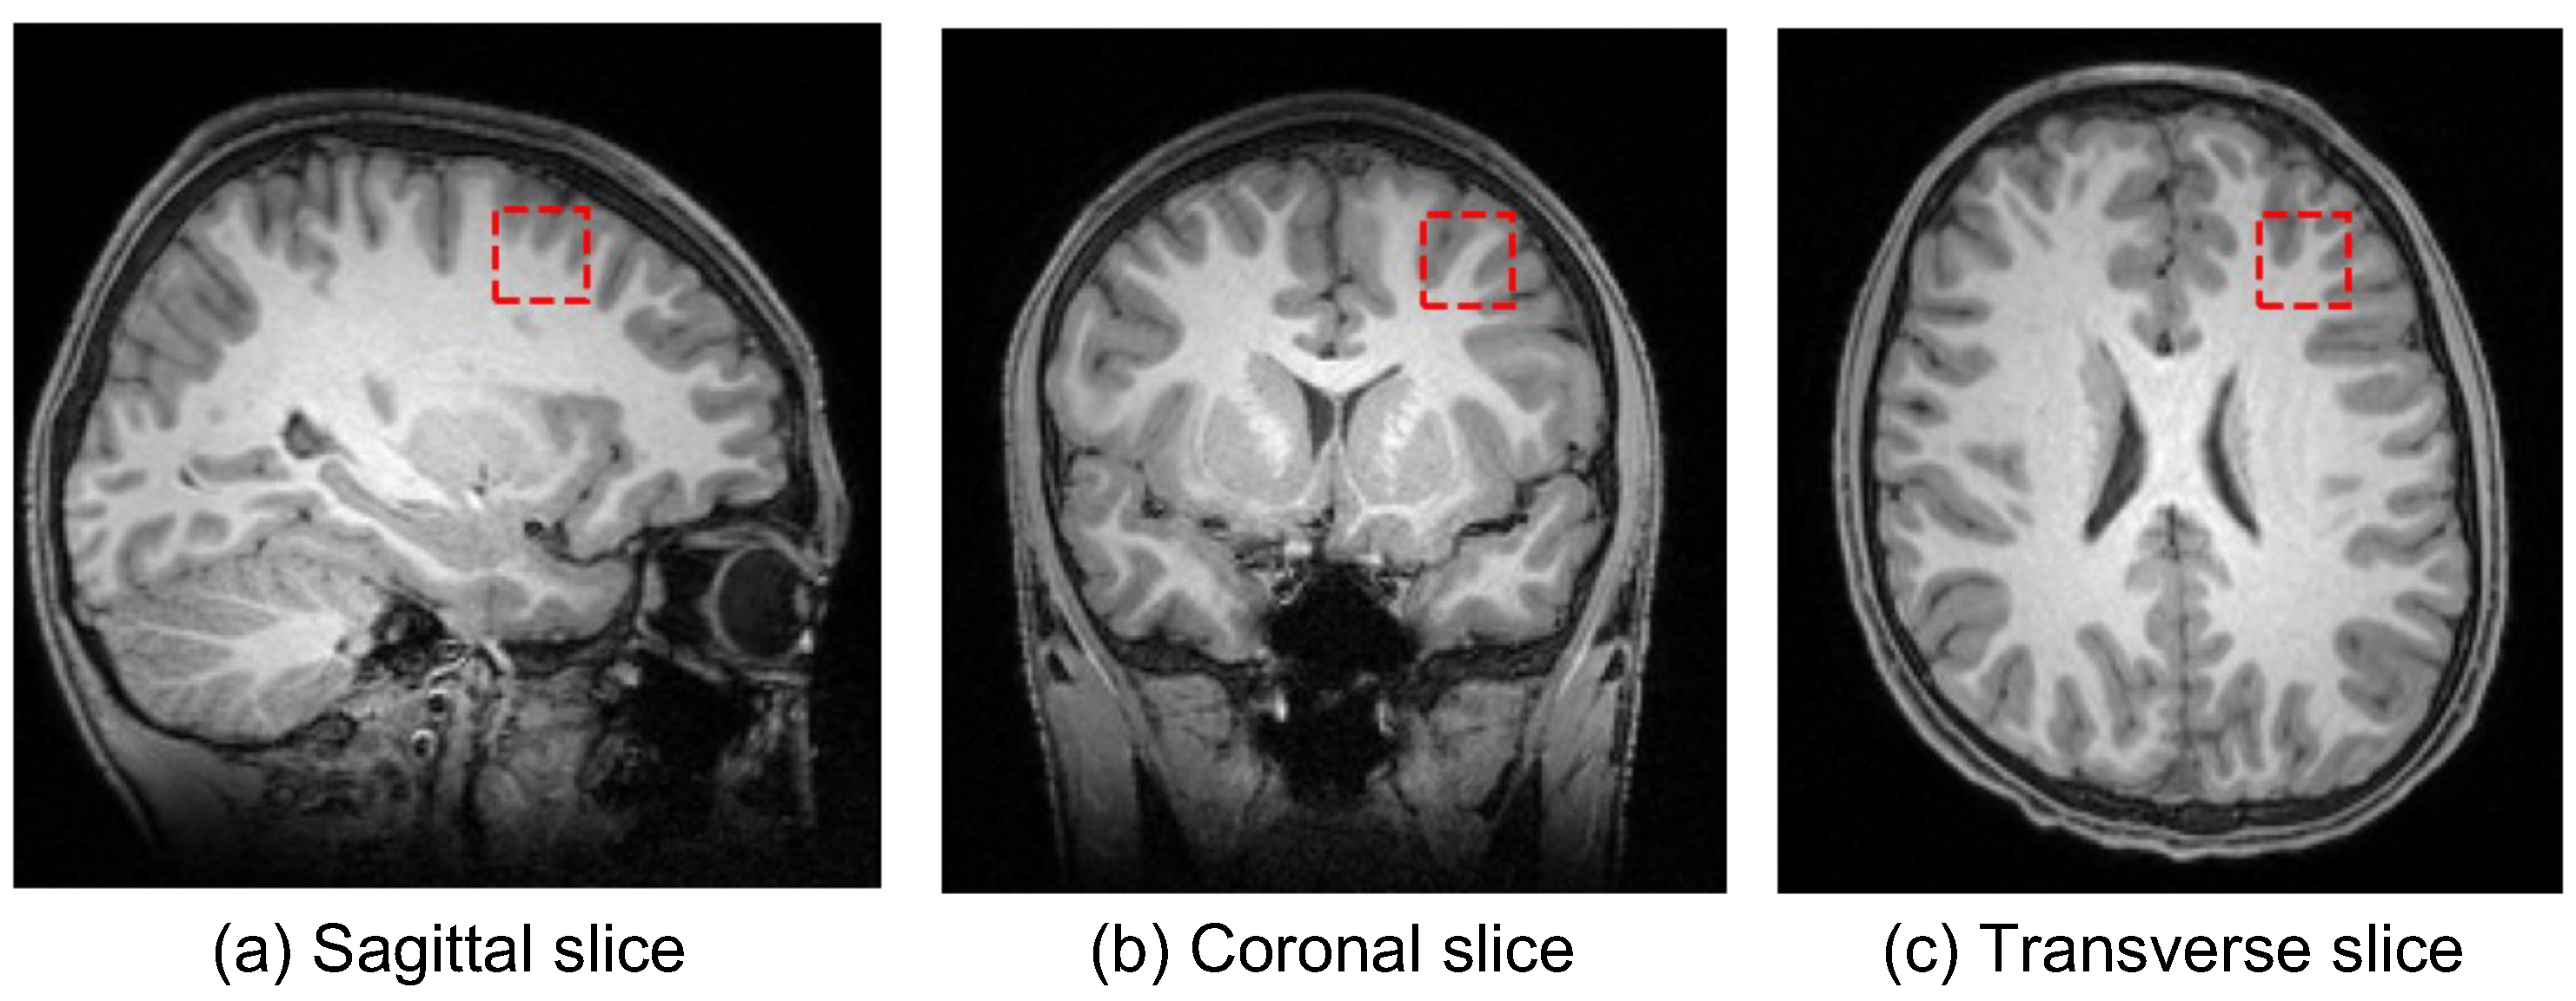

In the United Kingdom, 16-y-old adolescents can choose to stop studying math as part of their advanced, i.e., A-level, subjects. Towards a single dependent variable in the study, a math group consisted of 72 students who engaged in A-level maths. A non-math group consisted of 51 students who were not engaged in A-level maths. The used 123 MRI data were acquired at the Oxford Centre for Function MRI of the Brain (FMRIB) on 3T Siemens MAGNETOM Prisma MRI System equipped with a 32-channel receive-only head coil. And anatomical high-resolution T1-weighted scans were acquired using an MPRAGE sequence consisting of 192 slices, where repetition time ms, echo time ms, and voxel mm. The voxels of interest (VOI) of size mm were manually centered in the MFG based on the individual’s T1-weighted images while the participant was lying down in the MR scanner [3]. Slices of the T1-weighted MRI and the left MFG region in three different directions were shown in Figure 1.

Figure 1.

The T1-weighted MRI and the left MFG region. Three subplots are (a) a sagittal slice from left to right, (b) a coronal slice from top to bottom, and (c) a transverse slice from back to front, respectively.